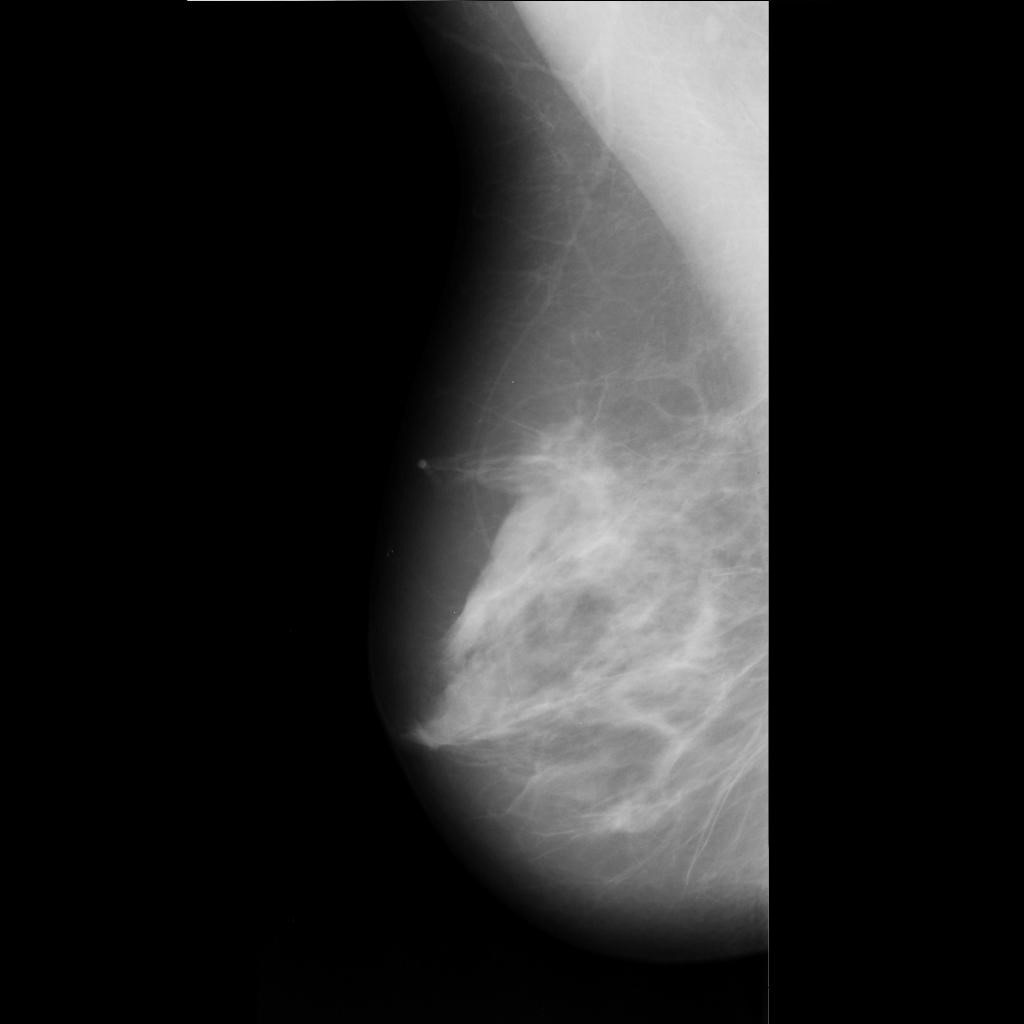

benign

malignant